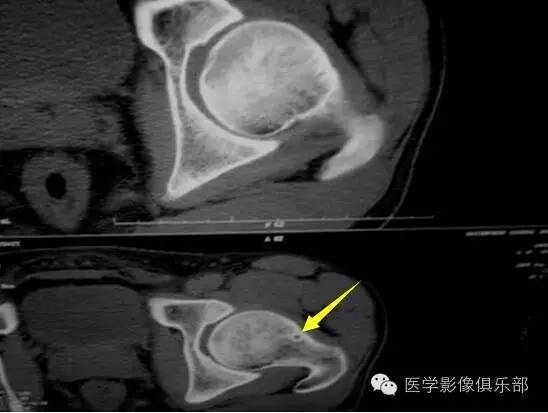

股骨颈疝窝

二者临床和影像学上表现相似,病理上也常很难区分,发病部位是主要的鉴别点。骨内腱鞘囊肿通常位于股骨头骨性关节面下方,局部关节面可伴增生硬化,相邻骨皮质少有裂隙。而股骨颈疝窝在病灶或相邻上下层面上大多可见与病灶相连的局限性裂隙样皮质缺损,不累及关节面。